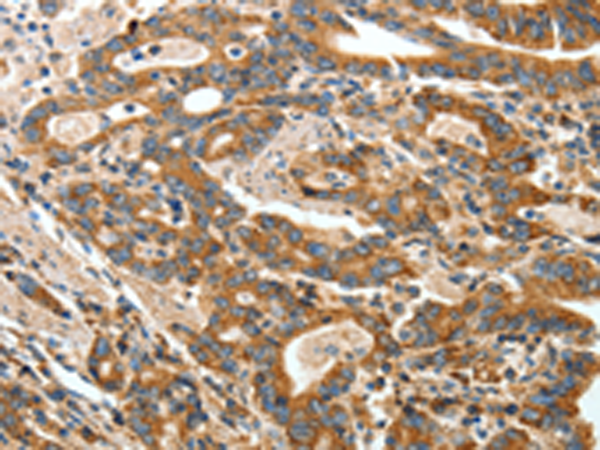

分类: 科研抗体货号: P00094别名: MGC104475应用: IHC反应种属: Human, Mouse